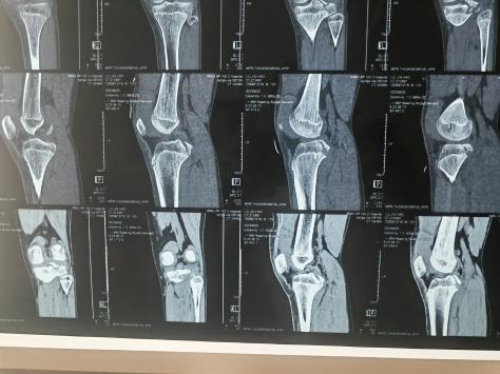

术前机器人设计手术入路